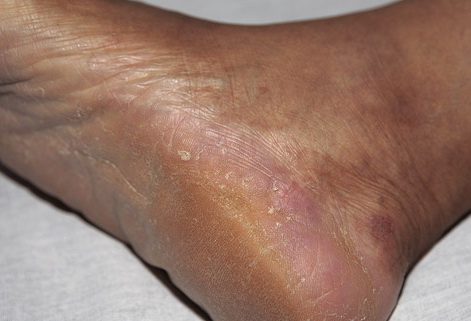

Chronic Hyperkeratotic Type.

Usually bilateral with patchy or diffuse scaling limited to the thick skin, soles, and the lateral and medial aspects of the feet, this is also known as “moccasin-type” tinea pedis. T. rubrum, the most common etiology, produces very few minute vesicles, leaving collarettes of scale less than 2 mm in diameter. Erythema is variable.